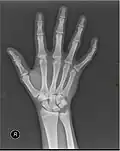

X-ray

Fracture

The neck of a metacarpal is a common location for a boxer's fracture, but all parts of the metacarpal bone (including head, body and base) are susceptible to fracture. During their lifetime, 2.5% of individuals will experience at least one metacarpal fracture. Bennett's fracture (base of the thumb) is the most common.[4] Several types of treatment exist ranging from non-operative techniques, with or without immobilization, to operative techniques using closed or open reduction and internal fixation (ORIF). Generally, most fractures showing little or no displacement can be treated successfully without surgery.[5] Intraarticular fracture-dislocations of the metacarpal head or base may require surgical fixation, as fragment displacement affecting the joint surface is rarely tolerated well.[5]

X-ray image of right hand with thumb on left.

Multiple fractures of the metacarpals (aka broken hand). (Right hand shown with thumb on left.)